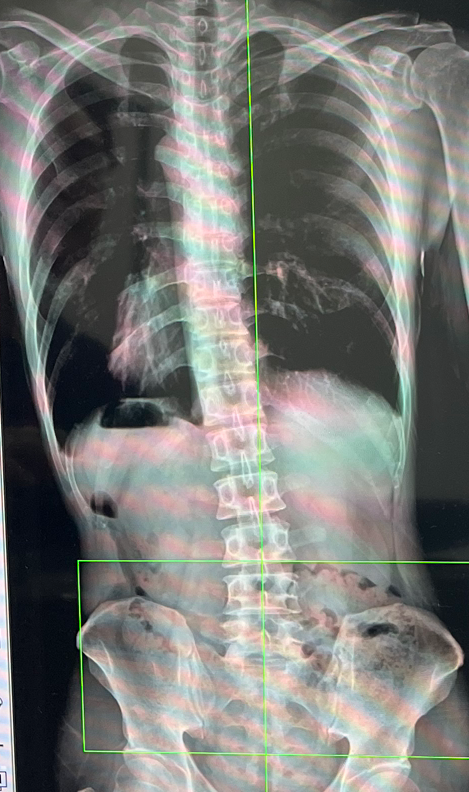

하루종일 앉아서 서서 일하느라 눌려있던 척추의 디스크들 쉴 수 있게 해주는 시간이었던 거죠.

누워서 자지 않고 앉아서 글을 쓴다는 건 업무+육아+기존 취미생활(기타, 드럼) 외에도 또 다른 부하를 주는 거였어요.

아이들이 아픈 날들, 자다가 깬 아이들을 많이 안아주고 생기는 통증도 있었고,

그게 심한 날은 허리가 좌우로 S모양으로 휘는 날도 있었느니, 더 이상 무시할 수 없었습니다.

다행히 정선근 교수님 유튜브, 책에서 배운 것들을 잘 지키는 삶을 살면서 회복되고 크게 아프지 않고 보낼 수 있었습니다.

아무튼 그렇게 허접하게나마 매주 (소위) 글쓰기 근육을 단련하던 제가 글쓰는데 시간을 할애하지 않게 되었지만, 그만큼 허리가 아프지 않게 되었어요.

허리 아프신 분들은 누워서 핸드폰으로 글쓰기 하시면 허리 회복에 방해 될 수 있습니다.

허리를 삐뚤게 하고 자는 게 되고, 아침에 일어나면 허리가 더 아플수도 있어요 ㅠ